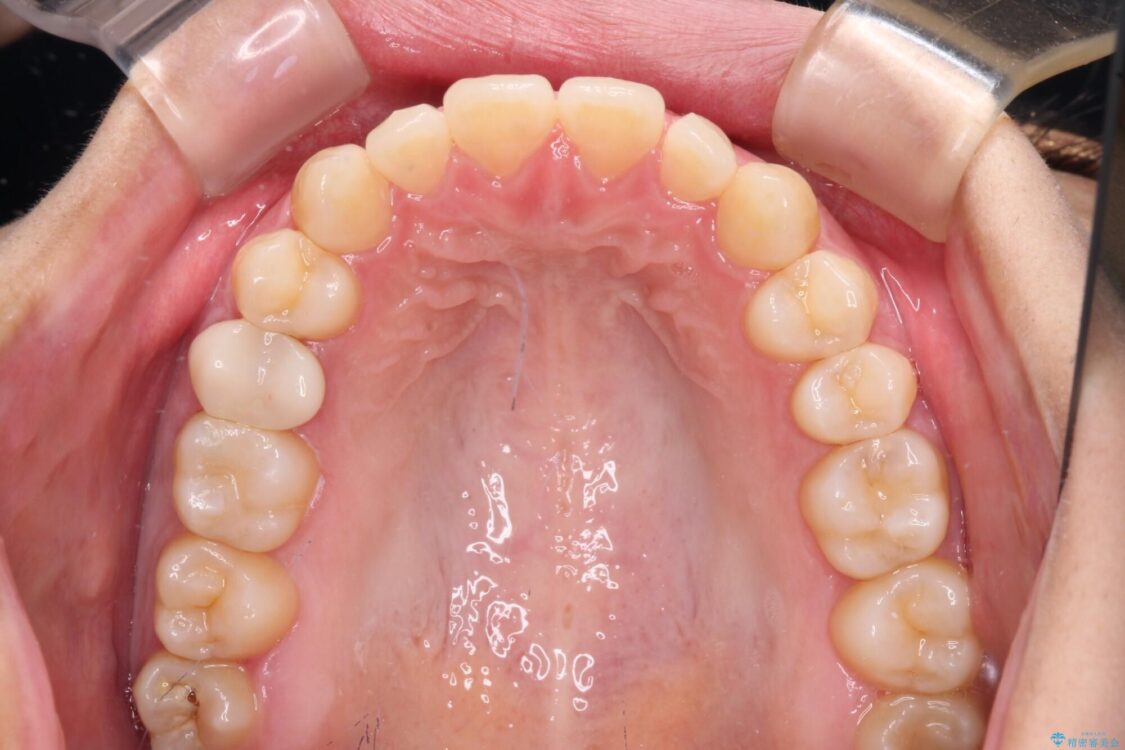

前歯の上下スペースと前歯の隙間を気にして来院された患者様です。

飲み込みや話をするときに舌を突出させる癖が強くあり、それが原因でスペースが空いていました。

舌癖を改善するためのトレーニングを行いながら、インビザラインにより上下の前歯の隙間を閉じていくこととしました。

治療後

• 隙間だらけの歯列 インビザラインで改善 治療後画像